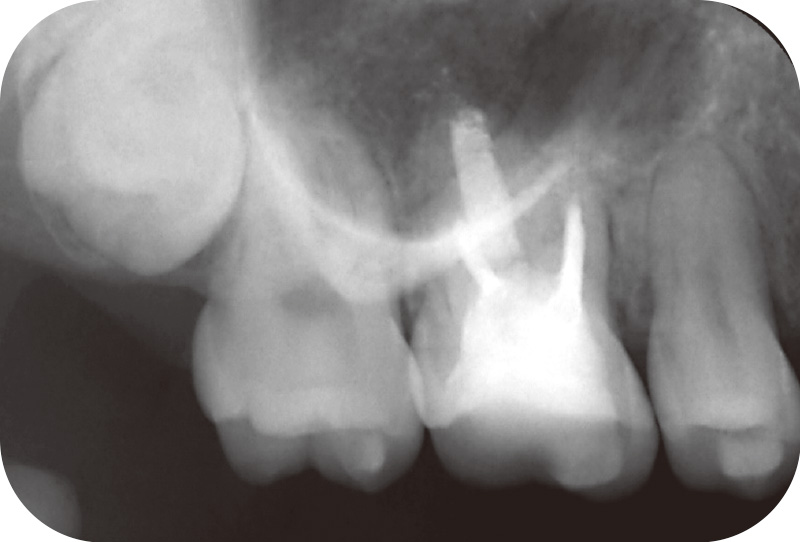

症例1-2 初診時CBCT画像。口蓋根に外部吸収(矢印)

(Veraviewepocs 3Dfにて撮影) -

患者は27歳女性。矯正歯科から根尖病変を指摘され当科を受診した。自覚症状はなかったが、近心頰側根および口蓋根の根尖部に骨欠損を認めた(症例1-1)。CBCTでは両根尖孔の開大と、口蓋根には歯根外部吸収を疑わせる歯質欠損が確認された(症例1-2)。